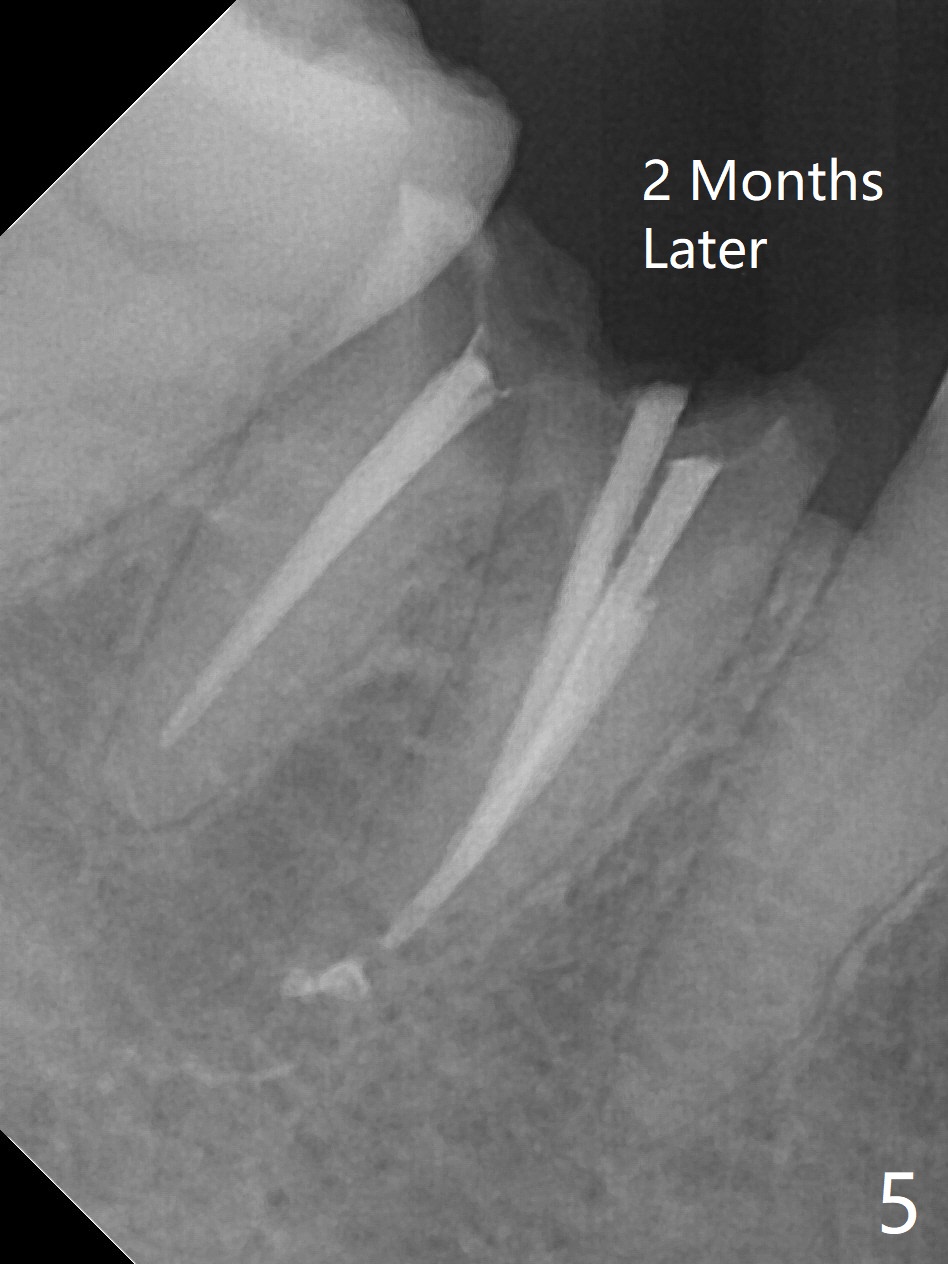

A 47-year-old woman with one carious tooth in her mouth (at #30) received RCT 14 years ago (Fig.1). The molar survives without crown for 3.5 years (Fig.2) and with crown for 8 years (Fig.3). The tooth has 2nd decays 10 years post crown (14 years post RCT, Fig.4 *). The crown dislodges 2 months later (Fig.5). Does the crown inadvertently reduce the longevity of the tooth simply hampering oral hygiene? After osteotomy until 4.5x10 or 13 mm IS drill with guide and 5 mm Bicon reamer free hand, place either 5x6 or 11 mm Bicon implant (Fig.6). Keep the black insertion plug to hold periodontal dressing or a provisional, which will be bonded to the neighboring tooth. Prepare PRFx1 for sticky bone around the not-so-stable implant. A 5x11.5 mm bone-level implant is planned by CT (Fig.7). Socket shield will be conducted to reduce buccal plate collapse. If the osteotomy depth is 10 mm due to limited mouth opening, place 4.5x6 mm Bicon implant. Otherwise 4.5x8 mm one. Return to Lower Molar Immediate Implant, Prevent Molar Periimplantitis (Protocols, Table), Trajectory II, Metronidazole Early Intervention Xin Wei, DDS, PhD, MS 1st edition 09/01/2019, last revision 11/10/2019